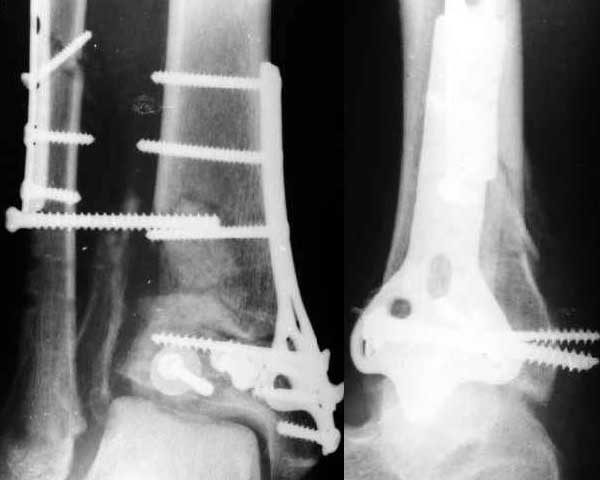

Полтора месяца назад мужчине 45 лет выполнена открытая репозиция дистального отдела большеберцовой кости и внутренняя фиксация (снимок 1).

На другой ноге - переломы нескольких плюсневых костей. Из-за сопутствующих урологических проблем через две недели перевели в другое учреждение, там был вынужден ходить с костылями с нагрузкой на обе ноги.При контрольной явке к нам через месяц обнаружилась несостоятельность фиксации (снимок 2). Какие выходы их положения можно тут предложить?